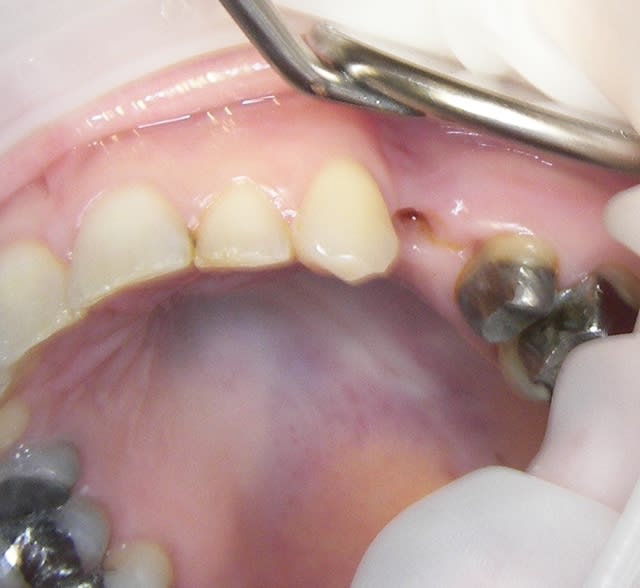

un exemple ce matin

j'en ai un autre cette AM mais probleme de carte sim

j'adore ce produit seul imperatif bien respecter le mode d'emploi